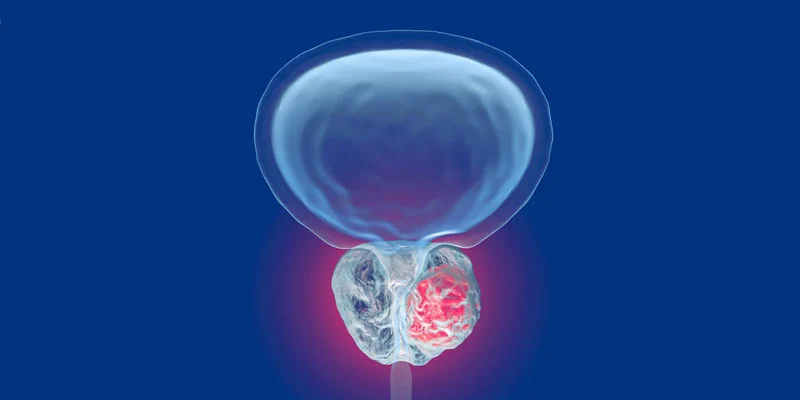

Benign Prostate Enlargement (BPH)

Minimally Invasive Prostate Procedures

Urological Cancers